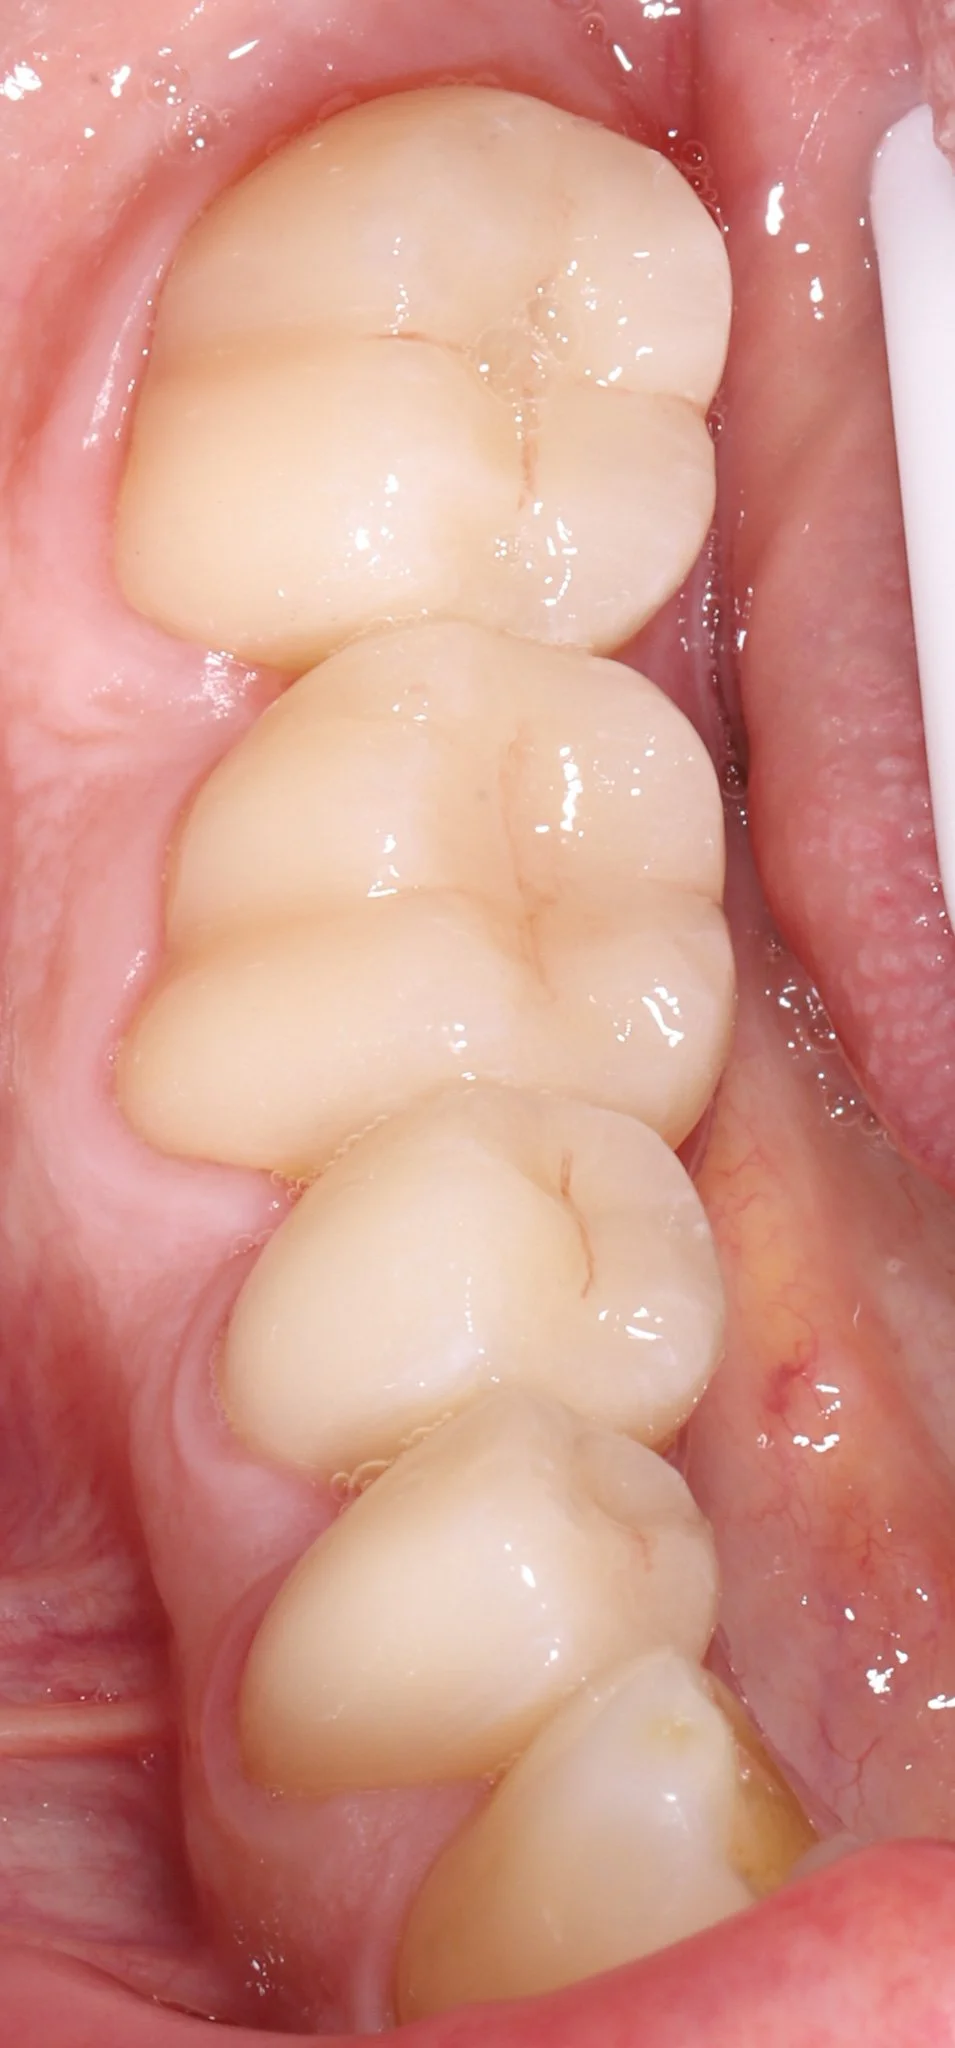

Close-up of molar teeth after restorations with bonded porcelain crowns showing optimal dental health.

After: New teeth blend seamlessly